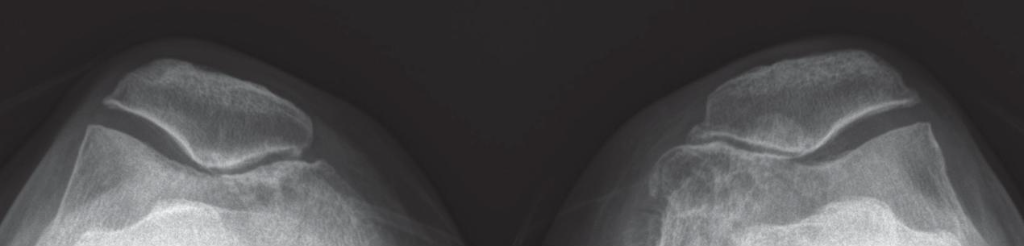

隨著病程的進展,影像學的發現顯示內側髕股關節的間隙逐漸變窄,這一現象在診斷過程中非常明顯(見圖1)。在一些嚴重的病例中,不僅內側髕股關節間隙持續變窄,髕骨內緣和股骨內側髁也會伴隨骨刺的形成。此外,有時還會在股骨內側髁的軟骨下方發現囊腫及骨質硬化的情況(見圖2)。

呂紹睿醫師指出,這些影像學變化有助於理解退化性膝關節炎的病理過程,並且為臨床診斷提供了關鍵的依據。對於患者而言,及早發現這些病變特徵,並採取相應的醫療措施,是有效緩解病痛和預防進一步惡化的關鍵。

▲ 髕股關節內側間隙明顯縮窄。(圖:時報出版)

▲ 內側髕股關節間隙縮窄,髕骨與股骨內側髁骨刺形成,股骨內側髁下囊腫與骨質硬化。(圖:時報出版)